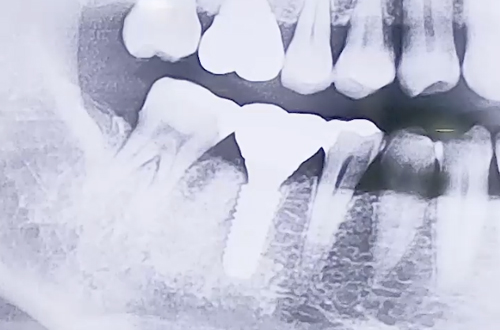

오른쪽 아래 큰 어금니가 굉장히 심하게 붓고 통증이 있는 상태로

내원해 주신 환자분의 사례로, 해당 치아의 흔들림이 심했습니다.

엑스레이를 찍어보니 어금니의 뿌리 중 하나의 주변으로 염증이 생기면서

치아를 단단히 잡아주는 힘이 약해져 흔들리고 통증이 있던 것이었는데요.

때문에 발치 후 임플란트를 시행하기로 하였으나, 발치한 자리 가운데에

식립하기에는 염증으로 약해진 잇몸이 고민스러웠습니다.

때문에 염증을 피해 살짝 옆쪽으로 심고, 염증 부분은 치료한 뒤

뼈이식으로 정리해 드리는 방향으로 치료해 드렸습니다.